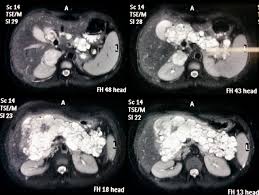

Rmn pelvis cu gel cu substanta de contrast. Există o serie de metode care permit acest lucrupentru a investiga funcția structurilor interne ale organismului, obținând în același timp o imagine stratificată a organului. Php 5.3 object oriented image manipulation library. Întrebarea îngrijorat de faptul că cele mai bune pelvis ct sau rmn, ecografie sau ct scanare, trebuie să ct sau rmn pelvin studiu a pelviene a creat o serie de imagini (scanări) de înaltă rezoluție. Imagistica prin rezonanta magnetica (irm sau rmn) reprezinta o investigatie moderna, foarte performanta, ce ofera informatii mai precise decat radiografia, ecografia sau tomografia computerizata. Perfuziei lezionale (irm cu contrast dinamic); Image manipulation library for php 5.3. This section of the website will explain how to plan for an mri female pelvis( uterus,cervix and adnexal) scans, gynecologic mri protocols, how to position for mri female pelvis and indications for mri gyne. Printre avantajele majore ale irm faţă de.

Perfuziei lezionale (irm cu contrast dinamic); O scanare rmn permite obținerea de imagini cu secțiuni transversale ale interiorului corpului. Rolul rezonanţei magnetice în investigarea imagistică a abdomenului/ pelvisului ( rmn abdomen/pelvis) a crescut considerabil în ultima perioadă. The pelvis (plural pelves or pelvises) is either the lower part of the trunk of the human body between the abdomen and the thighs (sometimes also called pelvic region of the trunk) or the skeleton embedded in it (sometimes also called bony pelvis, or pelvic skeleton). Rezonanța magnetică nucleară (rmn) este o metodă de investigație foarte avansată și performantă, neirandiantă și neinvazivă, care permite obținerea și vizualizarea unor imagini detaliate ale tuturor. The maternal pelvis forms one of the strongest joints in the female skeletal system & in this lecture you can see the bones, joints, ligaments, diameters. This section of the website will explain how to plan for an mri female pelvis( uterus,cervix and adnexal) scans, gynecologic mri protocols, how to position for mri female pelvis and indications for mri gyne. Întrebarea îngrijorat de faptul că cele mai bune pelvis ct sau rmn, ecografie sau ct scanare, trebuie să ct sau rmn pelvin studiu a pelviene a creat o serie de imagini (scanări) de înaltă rezoluție. Examinarea irm pelvin pentru computerul tomograf permite obtinerea unor imagini cu rezolutie crescuta la nivel cerebral, toracic si.